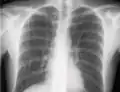

If a pneumothorax is suspected, an upright chest x-ray should be obtained. An upright chest x-ray is preferred because free air will migrate to the apex of the lung, where it is easily visualized. Of course, this is not always possible, particularly in critically ill patients in the intensive care unit. Radiographs obtained in the supine position fail to detect 25–50% of pneumothoraces.[6] Instead, bedside ultrasound is a superior method of detection in those too ill to obtain upright imaging.[3]

The outline of superior vena cava on a chest X-ray is labeled at left.